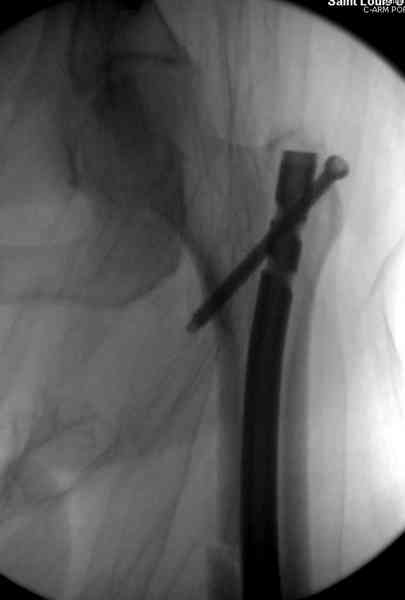

В операционной спереди гвоздя провел два 6.5 мм каннулированных шурупа, также через проксимальное отверстие антеградного гвоздя удалось провести шуруп.

Здесь представлены снимки больного 65 лет, поступившего с диагнозом перелом

бедра после автоаварии.

В первый же день произведено антеградное штифтованием DePuy Trochanteric Nail.

На второй день (7) обнаружен пропущенный перелом,

и проведены шурурпы через и спереди штифта без удаления.

Послеоперационные снимки